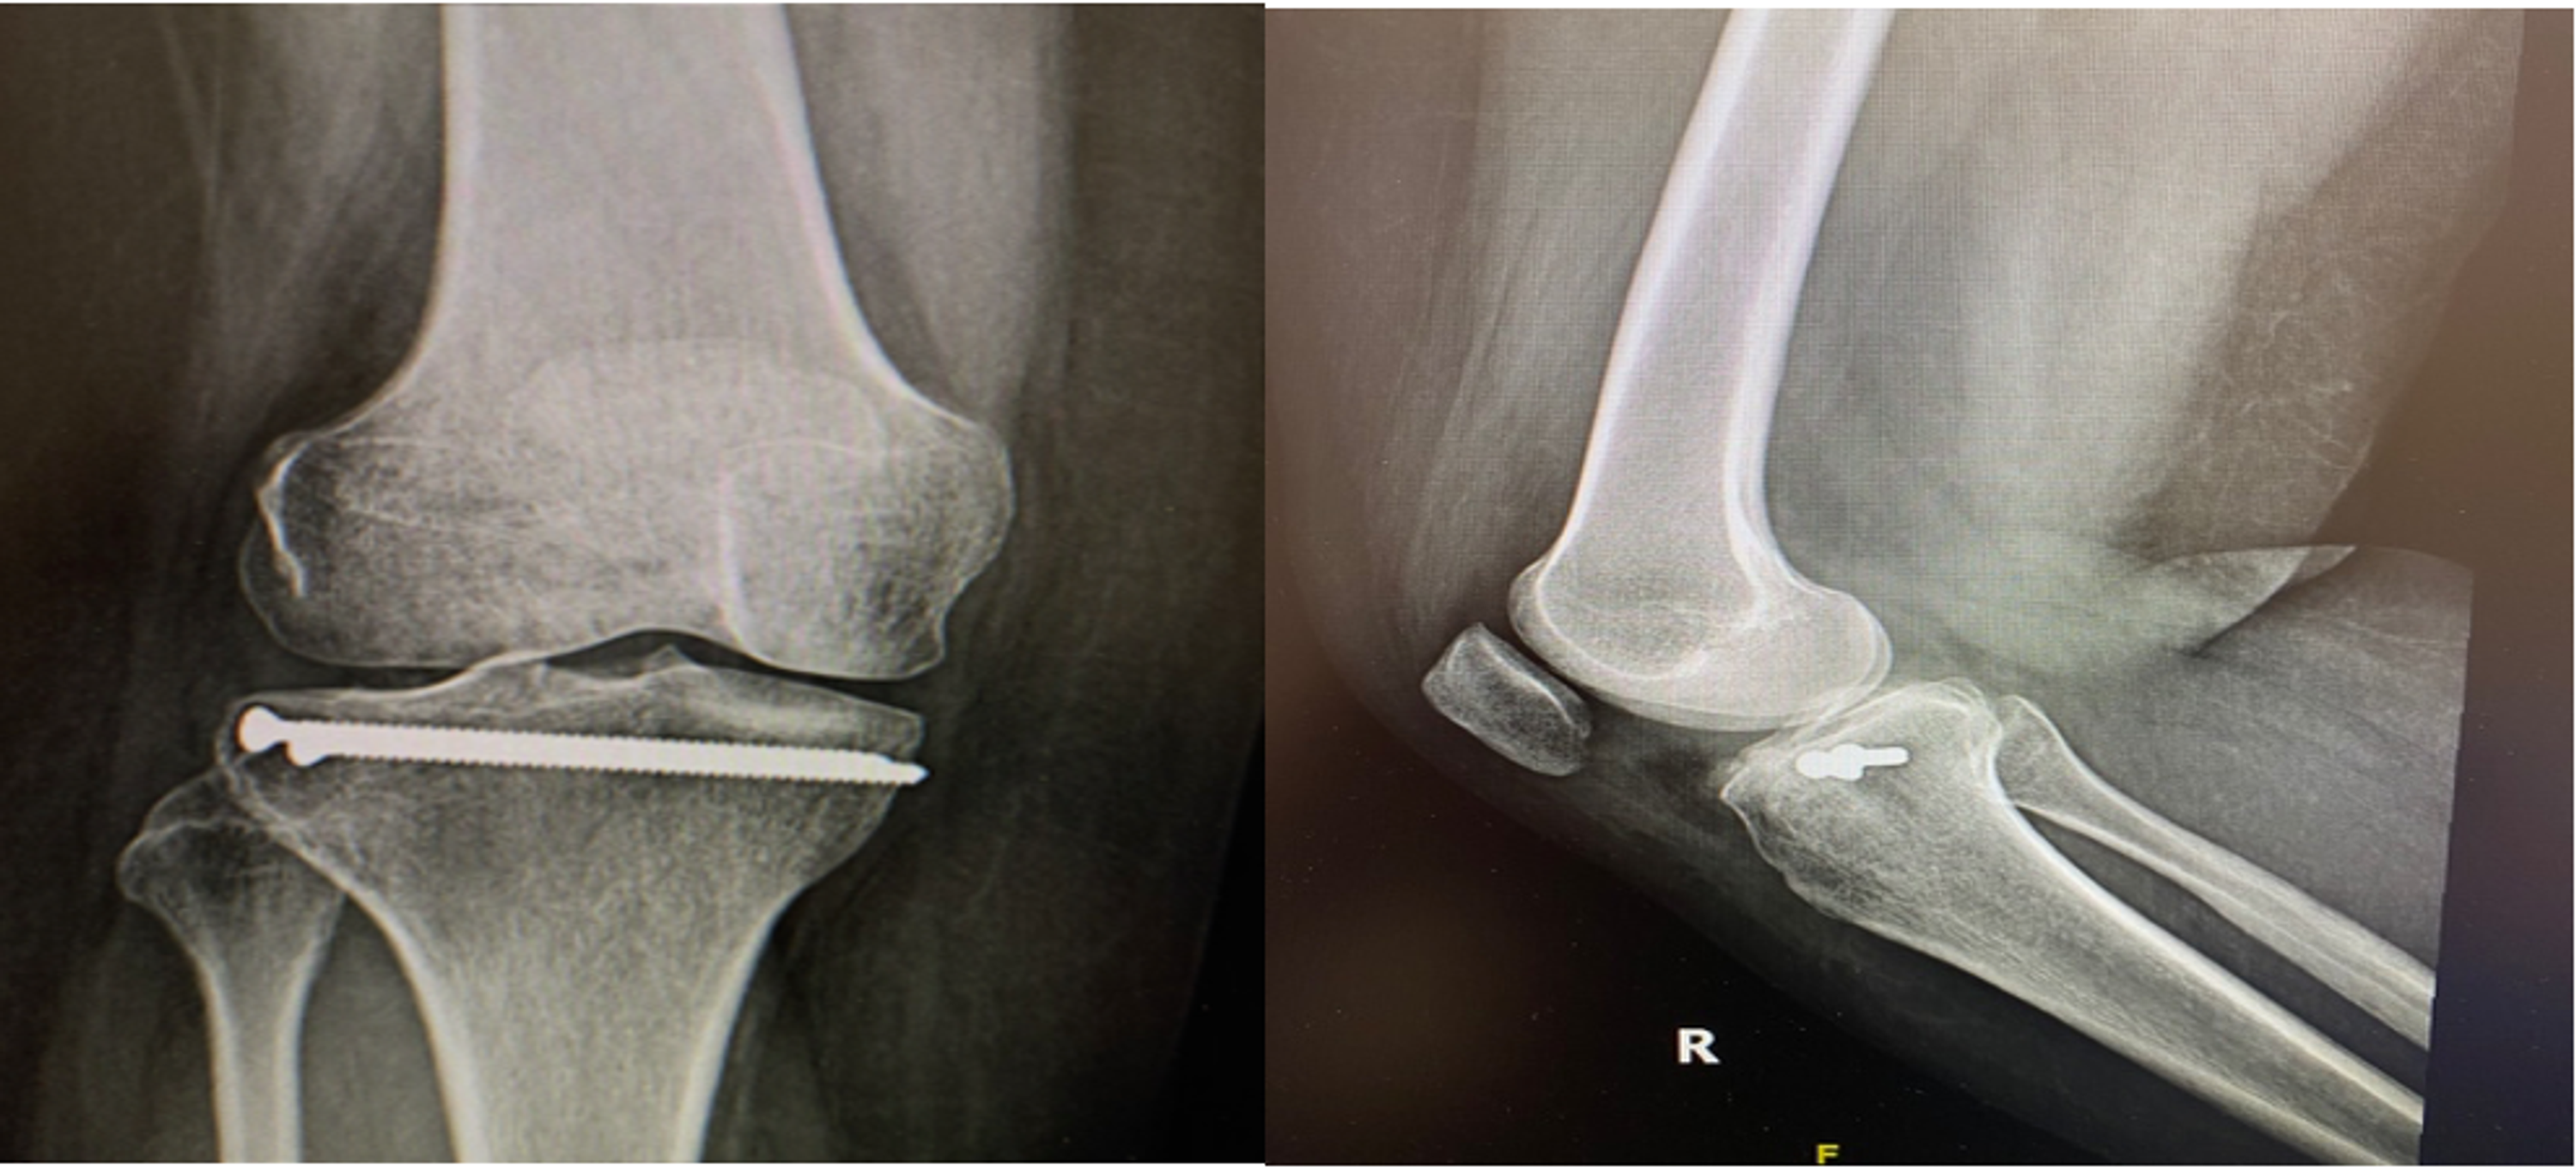

The resulting metaphyseal defect was grafted using bone allograft and a size 10 bioabsorbable screw was then introduced through the reamed bone tunnel to support the impacted bone below the reduced articular surface. In addition, two percutaneous 3.5 mm cortical screws were introduced subchondral from lateral to medial. Final fluoroscopic images confirmed the anatomic reduction of the fracture. The skin was closed and a dry dressing applied. The patient was allowed to have an immediate range of motion as tolerated. Partial weight-bearing was recommended initially and full weight-bearing was allowed six weeks after surgery. The postoperative course was uneventful. The patient had recovered full range of motion and the wounds were barely visible. One-year X-ray showed healed fracture without any evidence of displacement or subsidence (Figure 4).